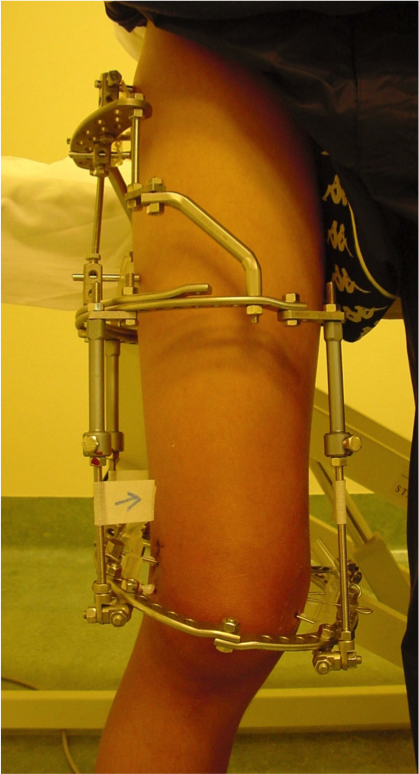

Inizio di correzione delle deformità

Inizio di allungamento

Correzione della deformità in valgo con ipercorrezione in varo

Risultato clinico a 3 mesi